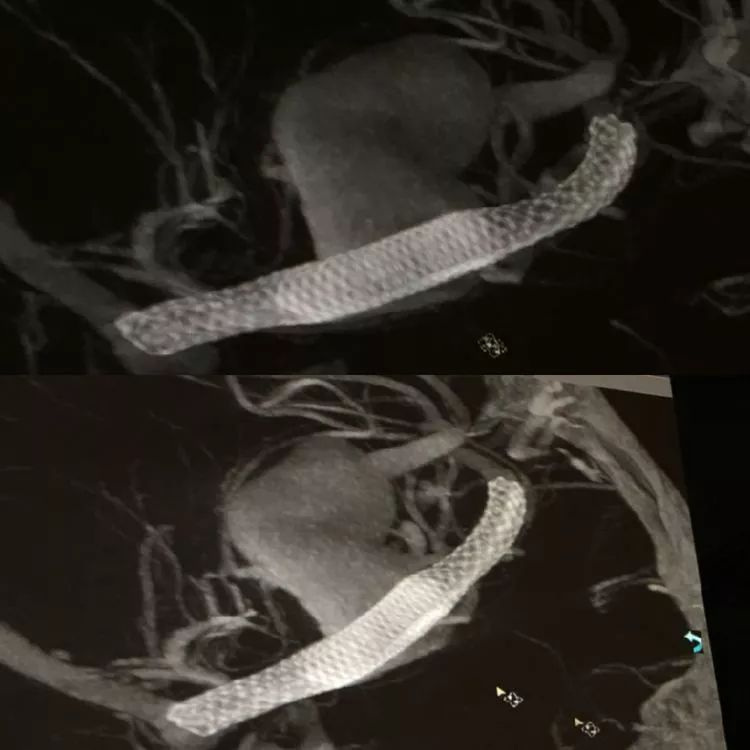

CASE 3 AN

-左侧大脑中动脉大型动脉瘤,上干累及,较为细小

-采用Pipeline shield,4毫米直径的具有磷脂涂层FD,动脉瘤区域稍外膨,支架网丝密度更大可能有利于愈合

-重点是血流导向重构治疗动脉瘤和保留上干